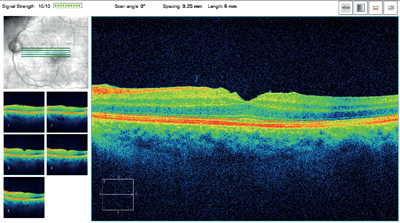

A 75-year-old gentleman was referred by his optician with marked left-sided macula pigmentation, querying wet age-related macular degeneration. Best corrected visual acuity (BCVA) in this eye was 0.1 LogMAR. The high-definition optical coherence tomography (OCT) scan showed an epiretinal membrane (ERM) but no signs of choroidal neovascular activity (Figure 1). When asked in more detail about any possible eye problems in the past, the patient recalled that he had had a vitreous haemorrhage in this eye some 13 years ago. On examination of the peripheral retina, a tear was found at one o’clock with a surrounding pigmented ring (Figure 2).

Figure 1: High-definition OCT showing a ‘puckered’ macula and ERM in the first patient.